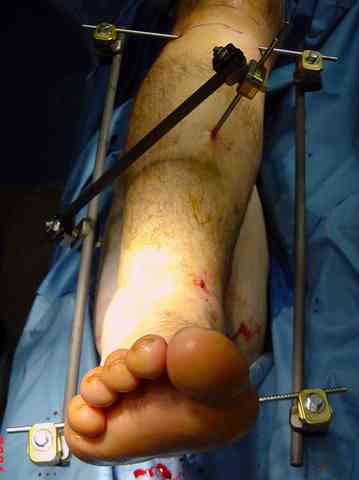

Яков изложил все необходимые аспекты лечения переломов пилона, и, не желая менять тему, решил выставить нашу точку зрения в двух клинических примерах.

При лечении внутрисуставных переломов типа "Pilon"

или "Tibial Plateau" на голени, применение простых

наружных фиксаторов типа "Spanning ExFix" или "Travelling ExFix" стал одним из стандартом этапного лечения.

В первые часы после поступления больным экстренно накладывается простой фиксатор из двух поперечно проведенных стержней или сооружается "Delta

Frame" в зависимости от места локализации, и проводится дистракция.

Преимуществ у временного фиксатора много, во первых больной независим, если по другим показаниям нет необходимости находиться в стационаре, то больной может быть выписан домой с возможностью в амбулаторных условиях оценивать состояния мягких ткани на готовность к операции.

Наружным фиксатором обеспечивается длина конечности, предупреждается вторичное сокращение мягких ткани, что является немаловажным фактором для заживления послеоперационных ран. Без фиксатора сокращенные мягкие ткани легко травмируется во время манипуляций, трудно будет провести репозицию, ухудшается местное кровообращение и сохраняется посттравматический отек.

Дистрагированные лигаментотаксисом костные фрагменты иногда организуются в нужном направлении и во время операции облегчается репозиция отломков.

Здесь выставлена пара случаев перелома пилона, оба

случая леченные этапным наружным фиксатором.

Второй случай фиксирован аппаратом Илизарова.